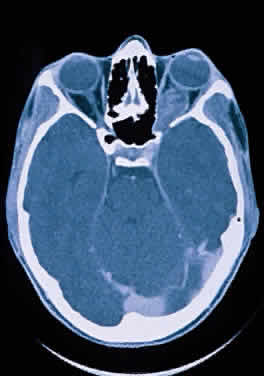

Hypoplasia of the optic nerve is also rare but is more common than aplasia (Figs. 13 and 14). It represents one of the most important developmental abnormalities of the eye and is increasingly recognized as a significant cause of visual deficit in children. Congenital nerve hypoplasia is a nonprogressive condition associated with a reduction in the number of retinal ganglion cells and axons. It may be either unilateral or more commonly bilateral and may involve the entire nerve or be segmental. Although a hypoplastic optic nerve is usually idiopathic, an increased incidence has been noted in the offspring of diabetic mothers and with the maternal use of phenytoin, quinine and, alcohol. Rare reports of an inherited disorder may be found in the literature. Although it may be an isolated abnormality, the hypoplasia is frequently associated with other anomalies—both ocular and nonocular. Additional ocular abnormalities include microphthalmos and congenital nonattachment of the retina. The most common nonocular abnormalities associated with congenital optic nerve hypoplasia include midline CNS structural defects, including septo-optic dysplasia of the septum and ectropia of the posterior pituitary, producing diabetes insipidus.

Fig. 14. Computed tomographic scan of head, showing hypoplastic left optic nerve.

In optic nerve hypoplasia, the optic disc appears gray and is about half its normal size but retinal vessels are present because the optic stalk is invaginated by mesoderm. The optic foramen is also small. Clinically, there may be strabismus, nystagmus, and decreased visual acuity. Severe cerebral abnormalities may be present but the hypoplastic nerve may be the sole abnormality.